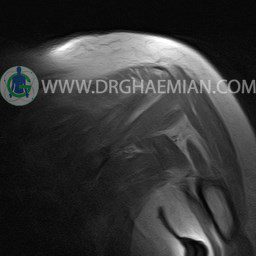

ام آر آی آتروفی عضلانی کتف بیمار

ام ار آی کتف یک روش تصویربرداری است که به وسیله آهنرباهای قدرتمند از قسمت کتف تصاویری ایجاد می کند. این نوع تصویربرداری از تشعشعات استفاده نمی کند. در این کیس آتروفی عضلانی کتف به همراه پارگی تاندون بالاخاری، بورسیت ساب دلتوئید و افیوژن مفصل دیده می شود.

– Complete tearing of supraspinatus tendon with grade 2 retraction and muscle atrophy

– AC joint hypertrophy with subacromial – subdeltoid bursitis

– Glenohumeral joint effusion

are seen.